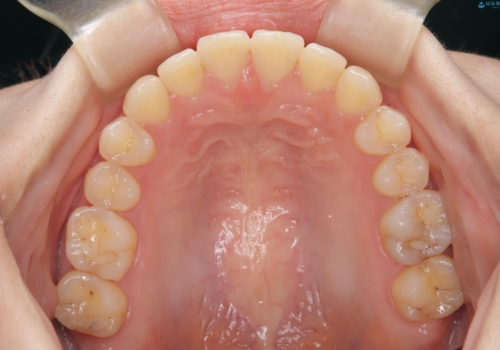

- 治療計画